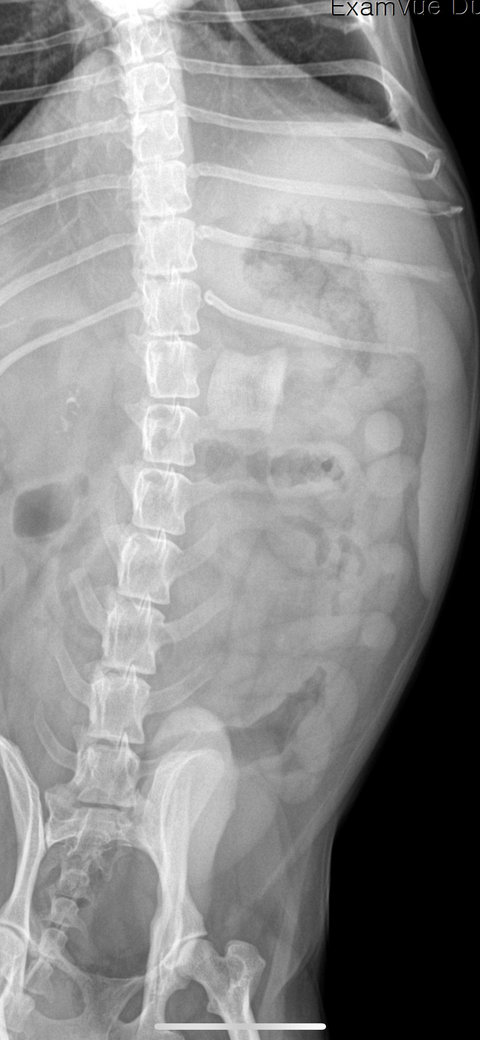

강아지가 3일 전과 2일 전에 족발뼈를 먹고 1일 전 새벽에 토를 12번 하여서 어제 병원에 방문 후 방사선 촬영을 한 사진입니다. 병원에서는 간수치도 좋지 않고 나이도 조금 있어서 변으로 유도해 보자고 하셨습니다. 대신 오늘 밥과 물을 줬을 때 강아지가 토를 한다면 병원에 다시 방문하여 수술을 하는 쪽으로 방향으로 가자고 하셨습니다. 토를 하지 않는다면 병원에 방문하지 않아도 될 거 같다고 하셨습니다. 오늘 강아지가 사료도 세 번 먹고 물도 많이 섭취했습니다. 그런데 강아지가 지금까지 똥, 오줌을 한 번도 싸지 않았습니다. 현재 이런 상황인데 문제가 있는 건 아닐까 걱정이 됩니다. 의견이 듣고 싶습니다. 추가적인 질문은 장 괴사는 어느 정도 시간이 지났을 때 일어나나요?

위 유문부 / 장 초입에 보이는게 족발뼈로 유추되며, 급이 후 아직 장으로 내려가지 않은 상태로 보입니다. 뼈가 커서 내시경으로 제거는 난이도가 있어보이며, 족발뼈 특성상 분쇄가 어렵습니다. 익일 동물병원에 들리셔서 방사선 촬영 후 별다른 하강이 보이지 않거나, 위산으로 인해 족발뼈의 크기가 충분히 작아지지 않은 상태로 오래 지속될 경우엔 개복이 필요할 가능성이 있습니다.

추가로 언급하신 위장관 괴사의 경우는 위장관 폐색으로 인해 장 내용물의 흐름은 물론, 주변 혈관 및 신경계의 흐름이 방해되면서 나타납니다. 이 땐 식욕이 아예 없고 복부팽만이 보이면서 나타나는 것이 일반적입니다. 현재 사진만으로 정확한 진단은 어려우며, 1~2일 간의 시간차를 둔 상황의 방사선 사진을 수의사 선생님이 판독 후 치료계획을 세우실 것으로 보입니다.